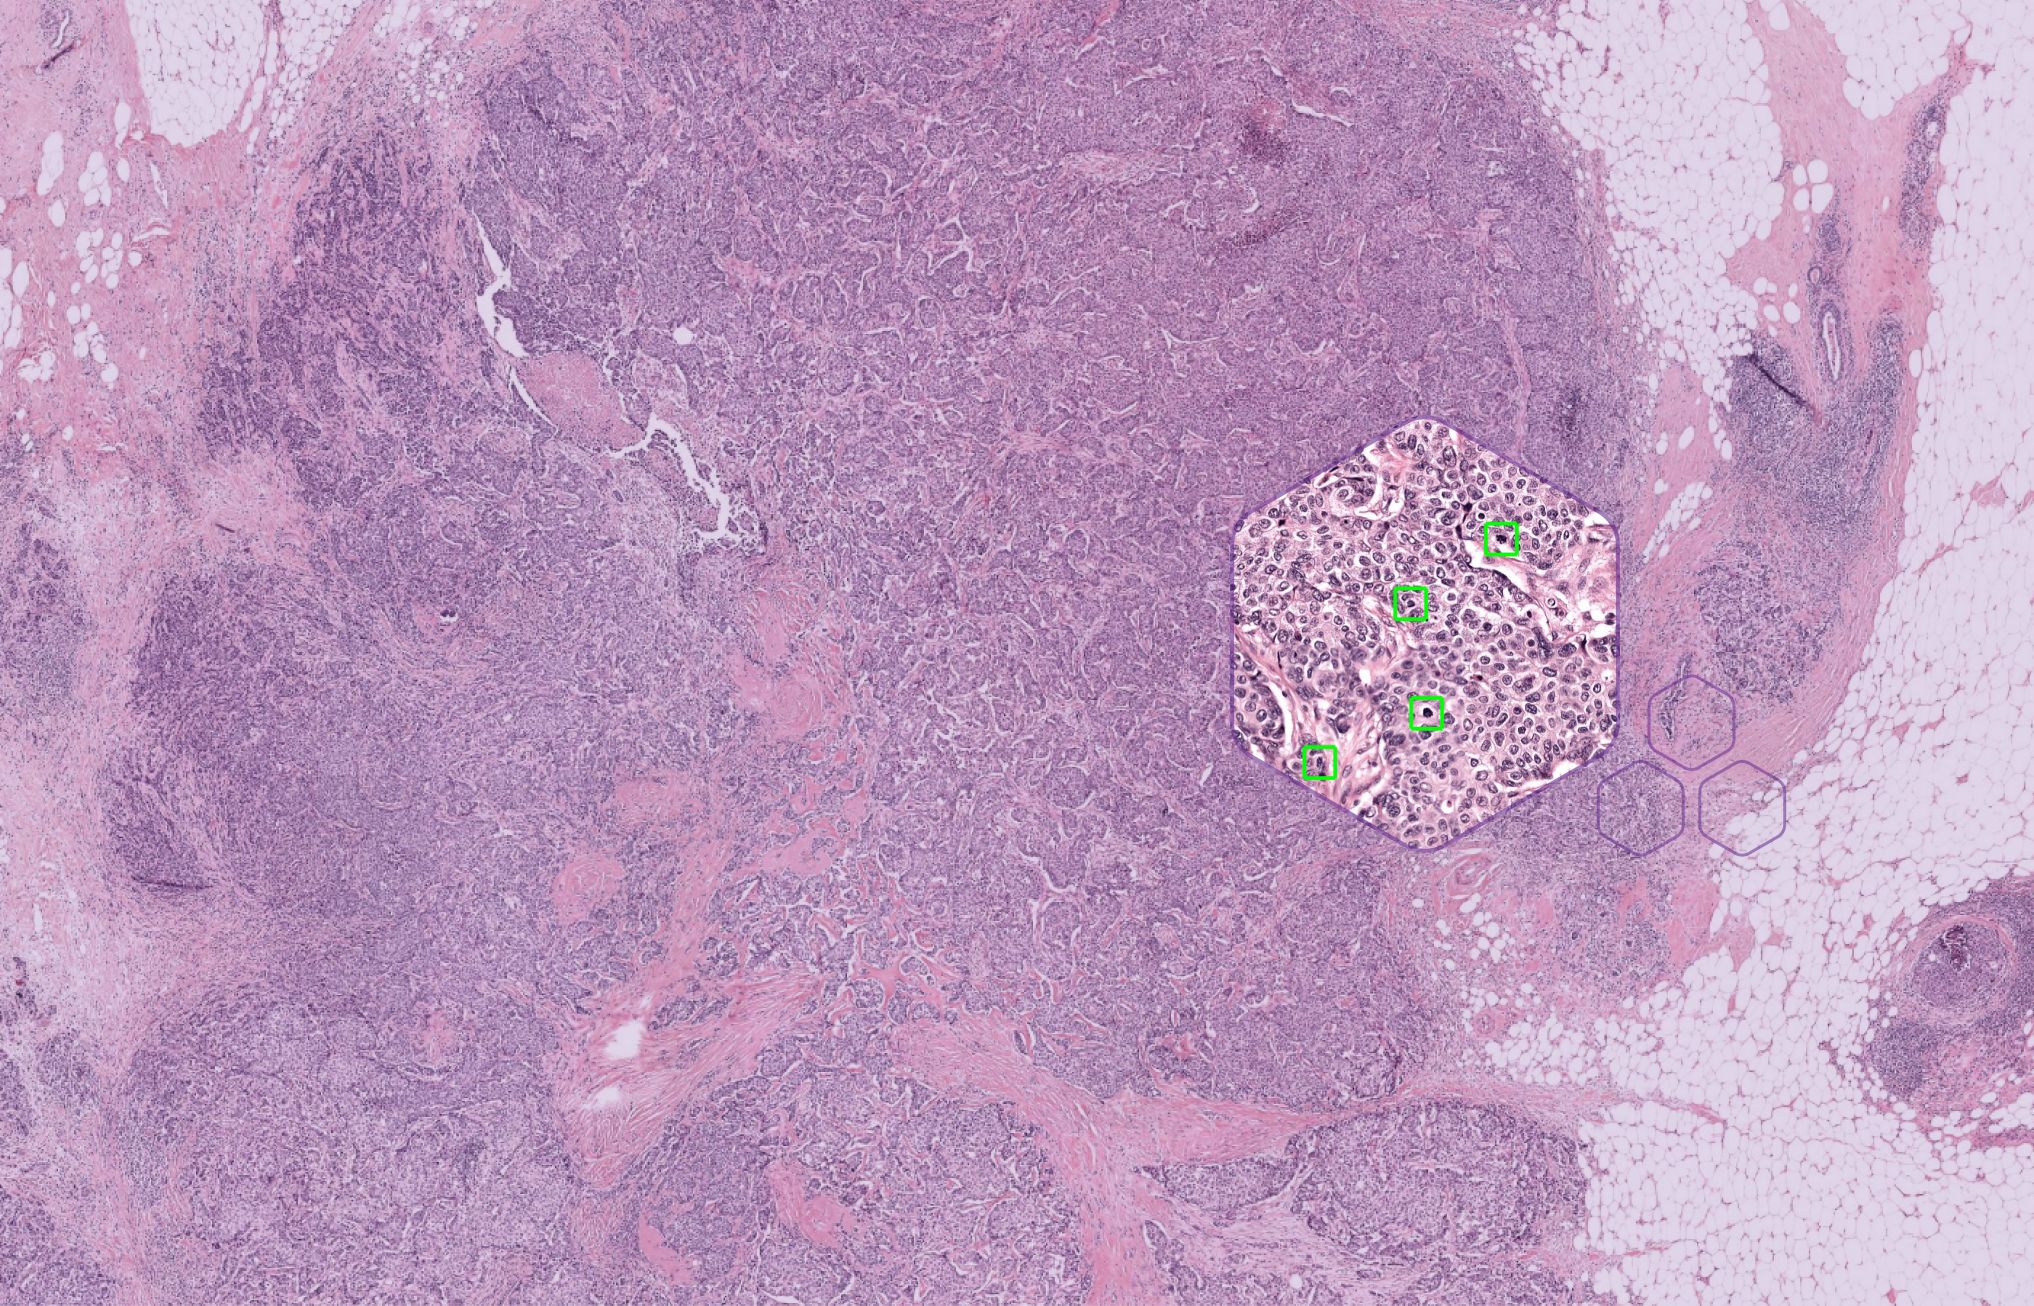

AI-assisted mitosis counting in breast cancer. A large-scale validation study.

25 March, 2024 • By Jeroen van der LaakAuthors Leslie Tessier, Cristina González-Gonzalo, David Tellez, Wouter Bulten, Maschenka C.A. Balkenhol, Jeroen A.W.M. van der Laak. Abstract Introduction Expectations surrounding AI in (breast) pathology are high. In contrast, little is known about the impact of AI on clinical practice,...